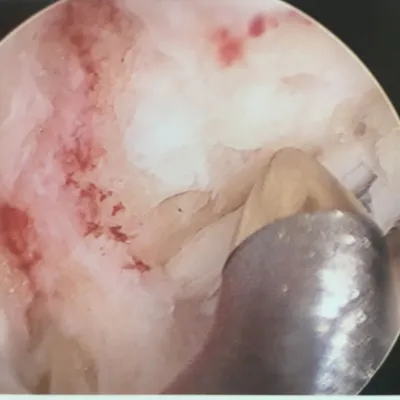

Series of Tibia OCD Microfracture

Pic during microfracture of tibial OCD.